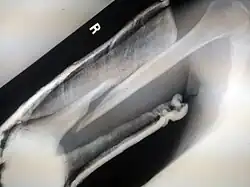

| Photo | Type | Description | Causes | Effects |

|---|---|---|---|---|

![]() |

Spiral fracture or torsion fracture | At least one part of the bone has been twisted (image shows an arm-wrestler) | Torsion on the bone[37] | May rotate, and must be reduced to heal properly |